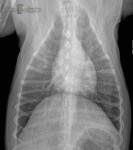

Latérale Gauche – 4 mois plus tard